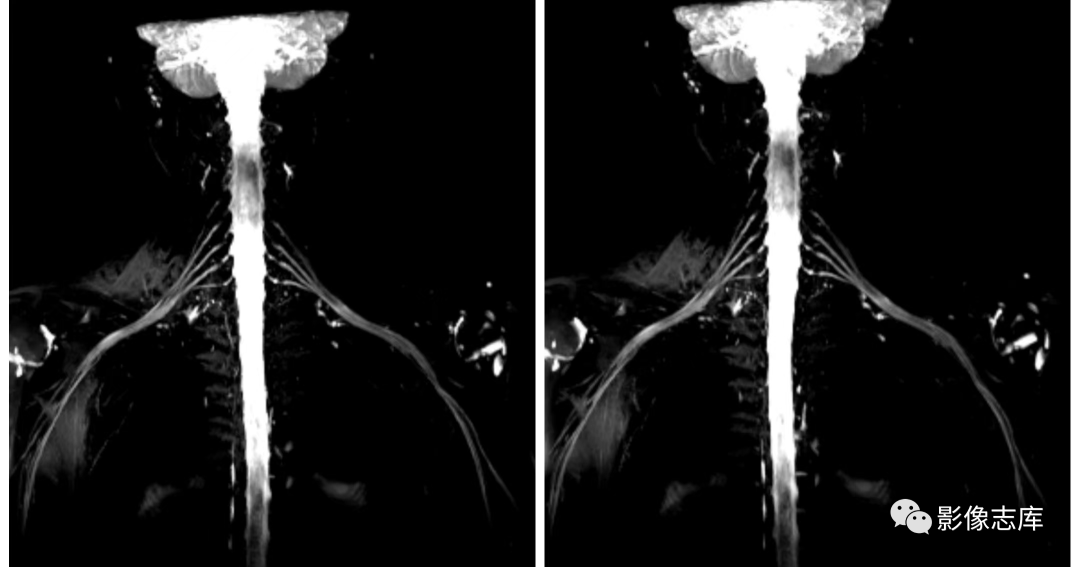

减轻模糊效应:SPACE序列在成像过程中使用了可变翻转角,大幅度增加回波链,减轻了T2衰减效应,避免了由于长回波链导致的模糊效应;

背景抑制:打药后进行T2 SPACE STIR cor 扫描,使背景抑制更彻底;

可实现各向同性:可进行3D等体素,扫描后可进行多方位重建,多角度观察臂丛神经;

高分辨:×450,明显提高图像空间分辨率;